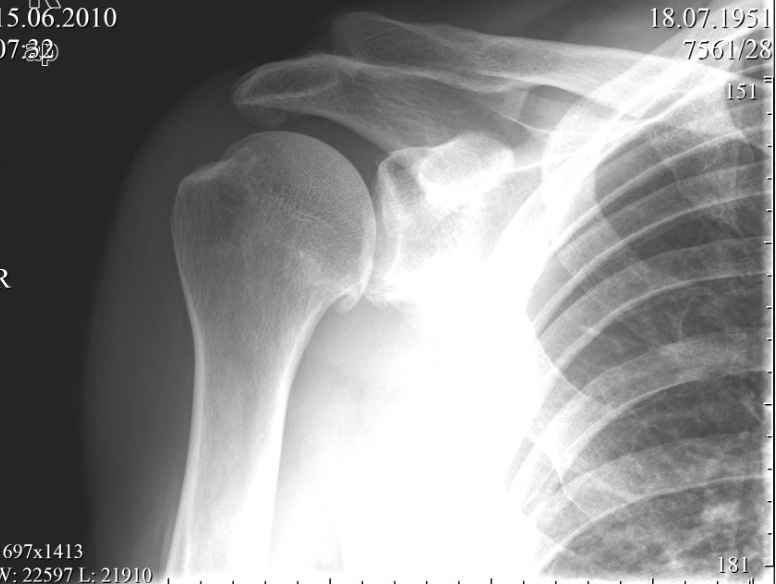

Пациент, мужчина, 59 лет обратился в июне с жалобами на умеренные периодические боли и хруст в области правого плечевого сустава. В анамнезе - 1,5 года назад упал, ударился задней поверхностью локтевого сустава, при отведенной правой руки в плечевом суставе и согнутом в локтевом. Обратился за мед. помощью, по месту жительства, сказали, что ничего страшного, повесили травмированную конечность на косынку.Тогда, в июне 2010года, когда я впервые увидел пациента, он щадил руку, было ограничение объема движений в правом плечевом суставе. Потому я предложил заняться лечебной физкультурой а потом посмотреть достигнутый результат.Сегодня в пациента восстановлен полный объем движений в правом плечевом суставе, боли сохраняются, но не такие выраженные, как раньше.Но при движении правой рукой стоит ТАКОЙ хруст, что слышен на расстоянии. Пальпаторно, при движении правой рукой,ощущается подвижность в акромиально-ключичном сочленении, и боли при отведении в правом плече более 120 градусов.Пациента не устраивает нынешние положение дел с его плечом. Хочет более радикального лечения.Я подумывая об операции, но побаиваюсь за результат. Нужно иссечь рубцы, низвести акромиальный конец ключицы (а она будет "пружинить")и фиксировать крючковидной пластиной к акромиону, не исключается выполнение акромионопластики. Удержит ли пластина и удержатся ли взаимоотношения в акромиально-ключичном сочленении, после удаления пластины?Тут вспомнился разговор с профессором Джолдасом Кулджановым, о необходимости восстановления клювовидно-ключичной связки. Хотелось бы освежить этот разговор в своей памяти и попросить профессора найти время и рассказать еще раз о целесообразности и технике восстановления клювовидно-ключичной связки, ну выслушать мнение коллег по Ортофоруму.С уважением Шушания Батал.

По снимку не создается впечатление о проблеме с корако-акромиальной связкой (может быть Тосси 1-2), которая не требует реконструкции.

А нет ли других проекций сустава? - нечеткая тень под акромионом позволяет подозревать кальцифицирующий тендинит - тогда высока вероятность окончательного "самоизлечения". А к акромиально-ключичному сочленению наверно придираться не стоит, хотя можно попробовать ввести анестетик и посмотреть результат

На представленном снимке нет данных за повреждение акромиально-ключичного сустава.

Имеется артроз плечевого сустава 2 ст. Под акромиальным отростком лопатки имеется крупное костное образование: или остеофит, или оссификат в области старого повреждения ротационной манжетки плеча. Я думаю. здесь нужна артроскопия плечевого сустава. Отправьте больного в ортопедический центр по квотам. Если функция сустава сохранена в достаточном объеме, следует объяснить больному о необходимости консервативного лечениа артроза и убедить смириться с хрустом.

Возможно у вашего пациента было какое-то повреждение АКС. Об этом говорит

состояние небольшого подвывиха, вторая степень - суставные поверхности

находятся друг против друга с небольшим смещением ключицы. Смещение

оценивается по нижней поверхности АКС. Но на рентгеновском снимке бросается

в глаза дегенеративные изменения. Первый из них это остеофит в нижней части

головки плеча (французская бородка) помечен стрелкой. Эта находка говорит о

артрозе плечелопаточного сустава. Вторая находка большой остеофит

акромиального отростка - помечен пунктирной линией. Данная находка говорит о

существующем давлении на сухожилия манжетки вращателей и вероятно разрыв

сухожилий. Rotator cuff syndrome Rotator cuff tear. Полный разрыв сухожилий

может объяснить хруст при движении в плечевом состоянии.